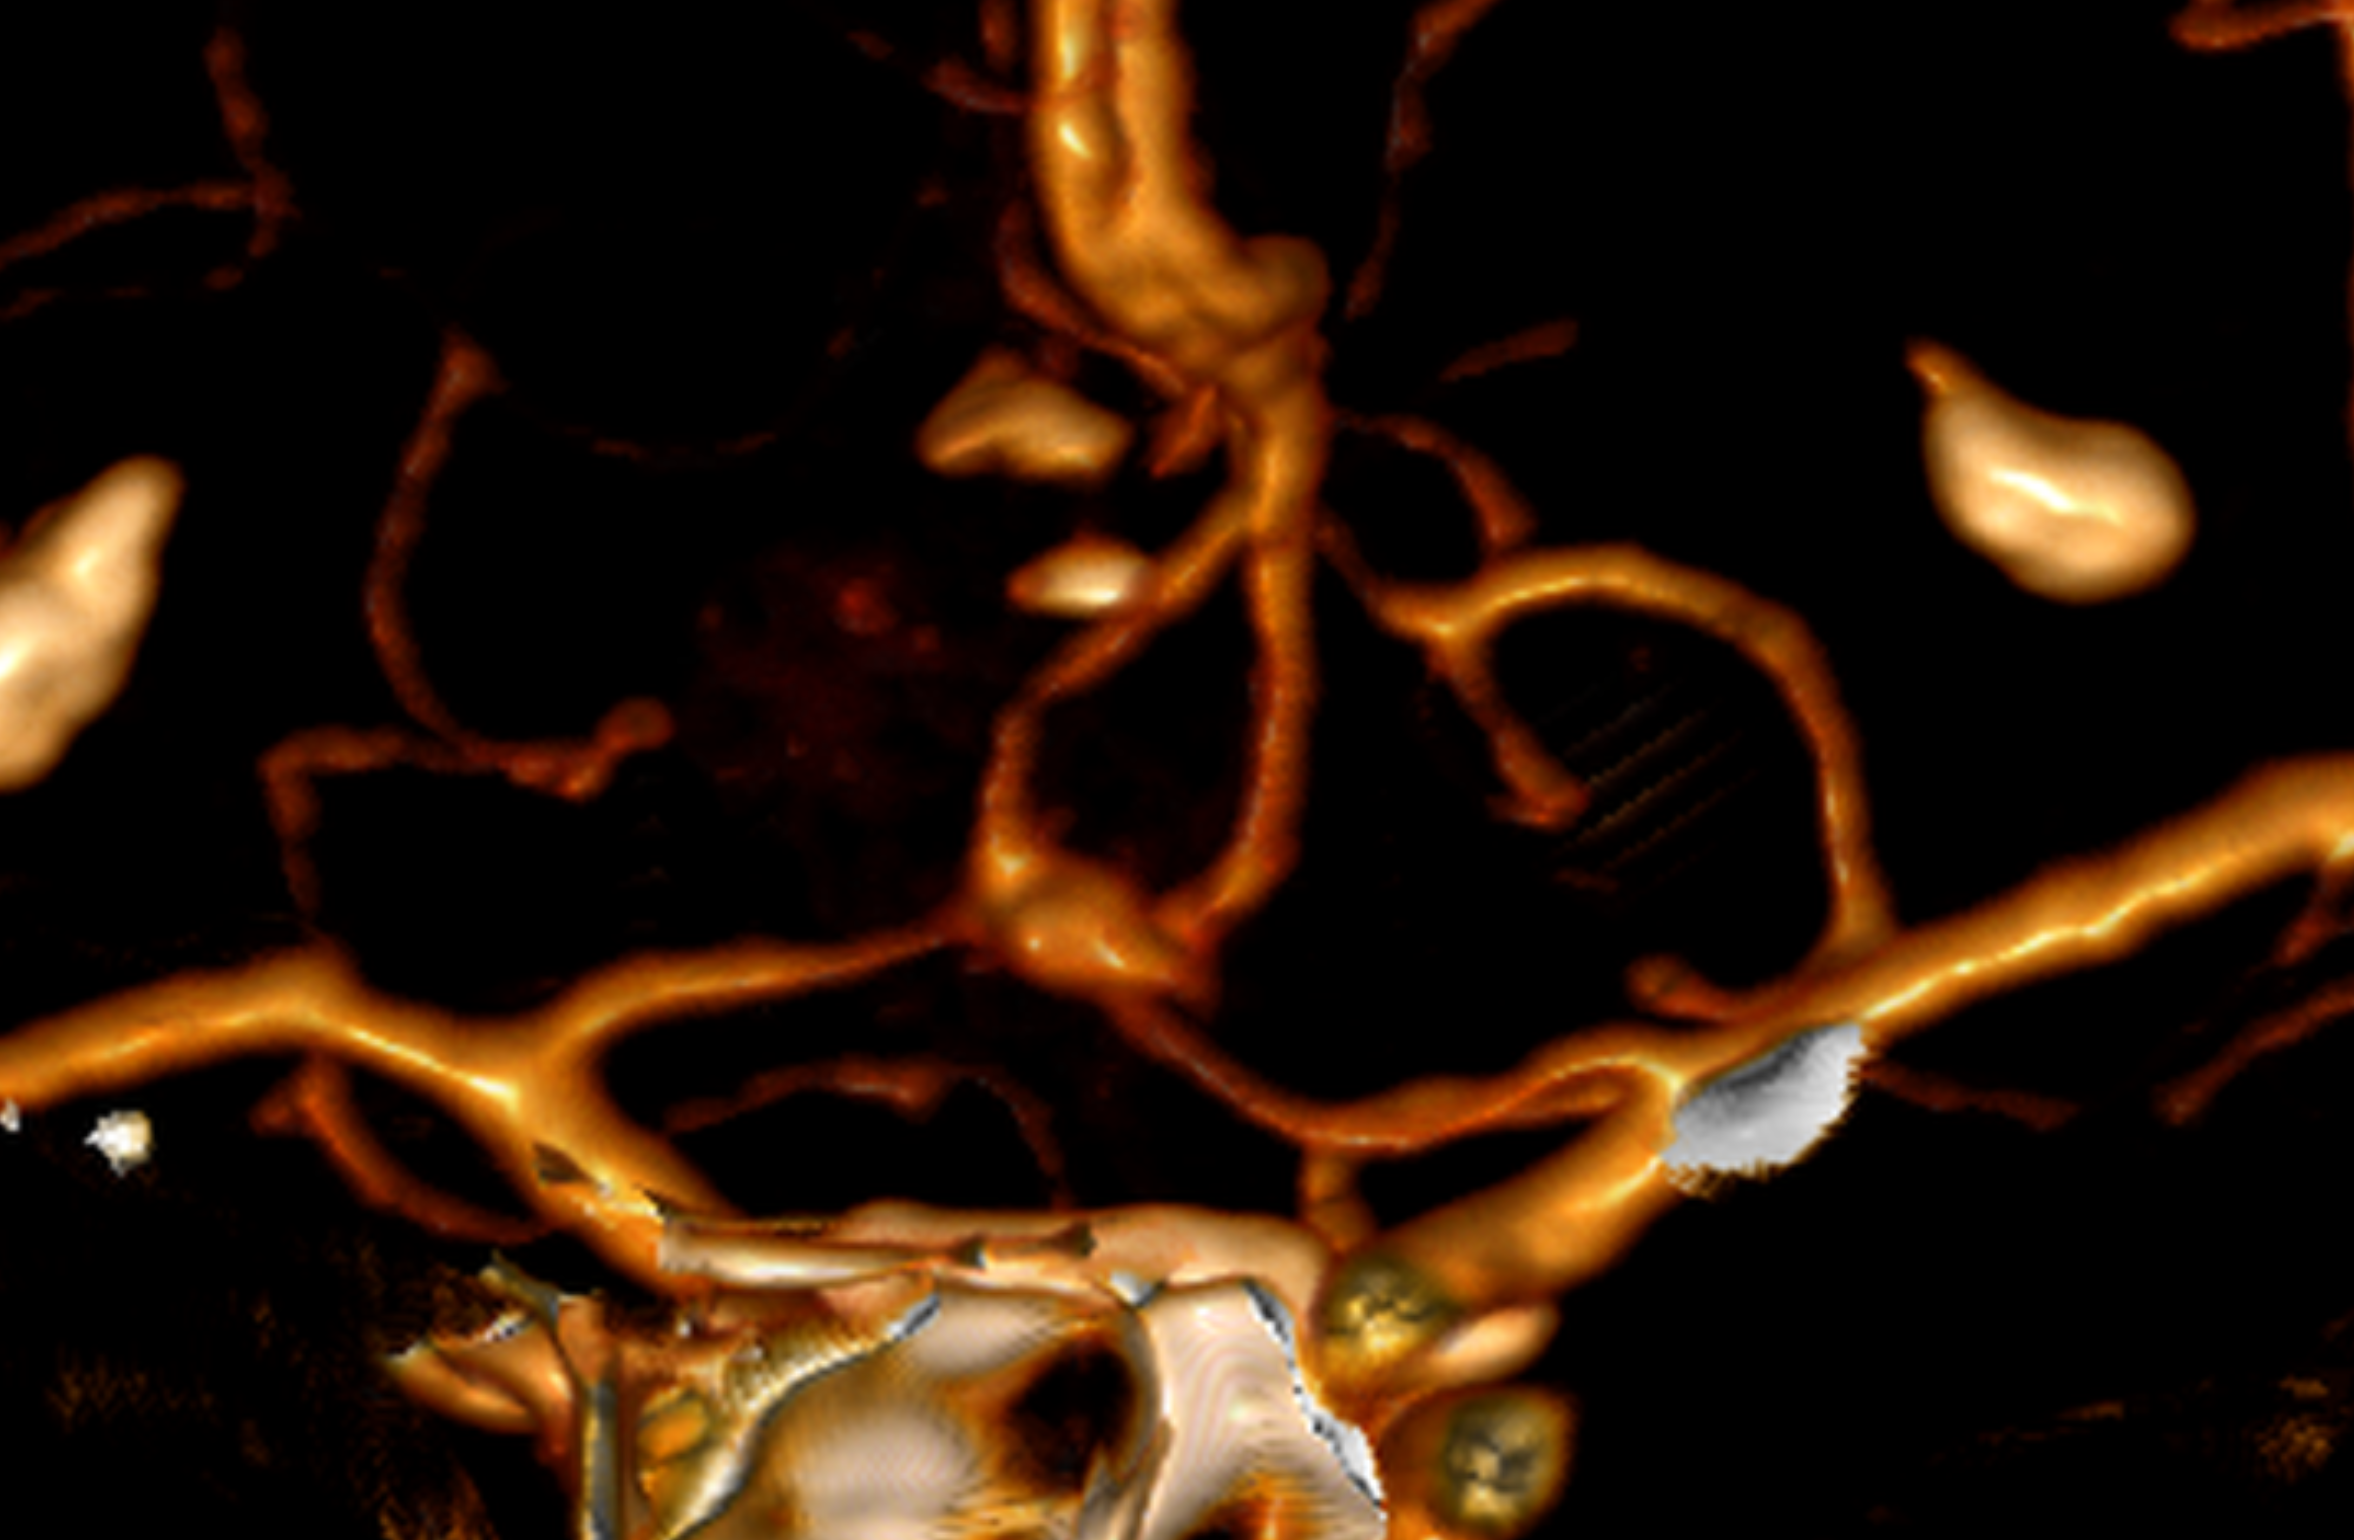

Se pueden usar varias modalidades de imagen para definir la MAV. La TC (Tomografía) y su variante Angiotomografía brindan información sobre la ubicación y la anatomía vascular estática, incluidos los vasos que irrigan y drenan la MAV. La resonancia magnética nos dice en qué parte del cerebro se encuentra la MAV y ayuda a medir el riesgo y los enfoques quirúrgicos y brinda información sobre hemorragias previas. La angiografía cerebral brinda información dinámica detallada sobre los patrones de flujo y el drenaje venoso. Es la prueba más sensible y poderosa, sin embargo, es técnicamente más «invasiva» y conlleva un riesgo muy pequeño de accidente cerebrovascular.

Aneurisma recurrente visto cerca de clips

Angiografía cerebral 3D que muestra un aneurisma